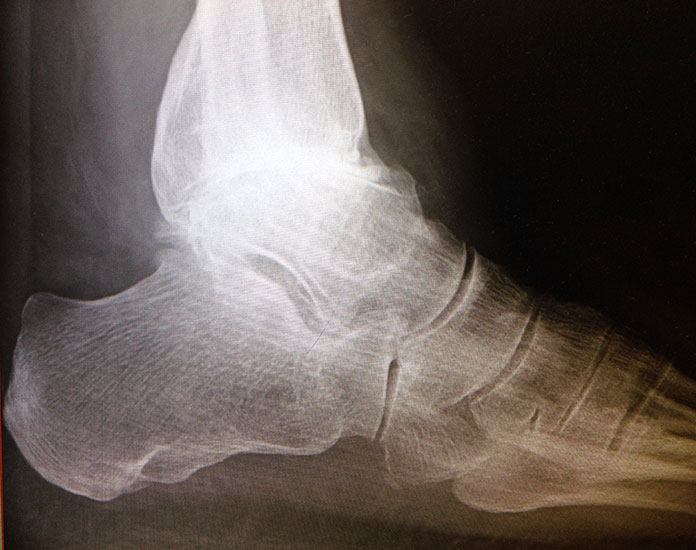

Erreichen eines schmerzfreien oberen Sprunggelenkes mit belastbarem und plantigrad aufsetzbarem Fuss (Abb. 1a und b) unter Verzicht auf die Bewegungsfunktion des oberen Sprunggelenkes. Operative Resektion der arthrotisch veränderten Gelenkflächen bis in den subchondralen frischen Knochen von Tibia und Talus. Fusion mittels Kompressionsschrauben oder Arthrodeseplatten, bedarfsweise Arthrodesenagel.

Abbildung 1a